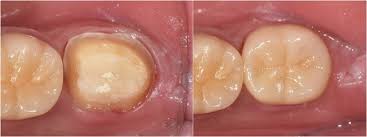

2. 크라운이란 무엇인가?

크라운은 손상된 치아 위를 씌우는 인공 보철물로, 치아를 외부 충격에서 보호하고 정상 기능과 자연 외형을 회복시켜 줍니다. 어금니는 내구성, 앞니는 심미성을 고려해 재료를 선택하는 것이 핵심입니다.

신경치료 후 치아는 내부 구조가 약해져 쉽게 깨질 수 있습니다. 크라운은 이를 보호하고, 씹는 기능과 심미성을 복원해주는 중요한 치료 단계로, 선택이 아닌 필수입니다.